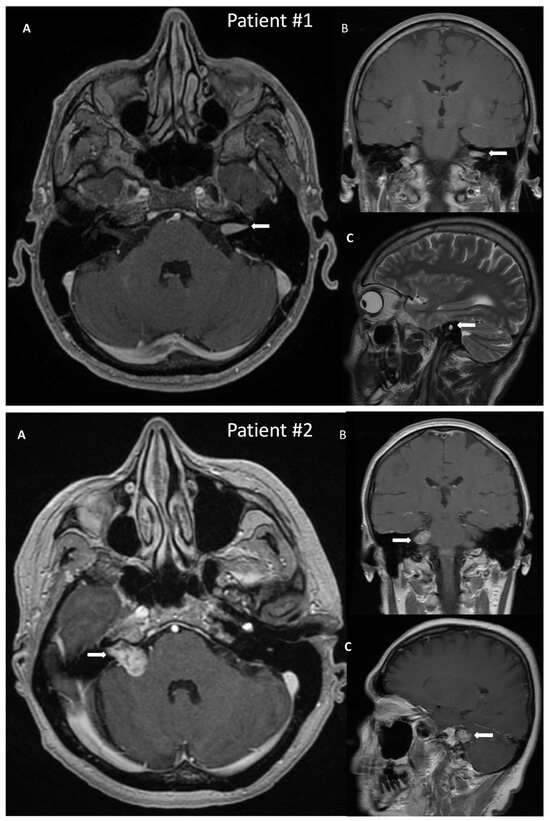

3.1.2. Case Example—Patient #2